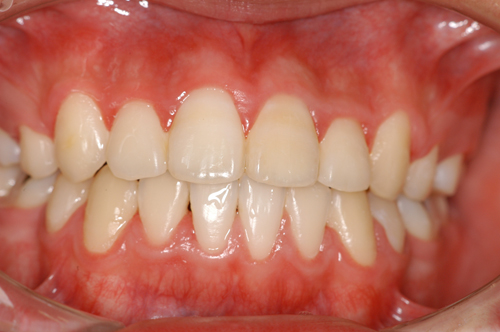

患者:14歳8ヶ月 男性

抜歯部位:上顎、第一小臼歯 下顎第二小臼歯

動的治療期間:18ヶ月